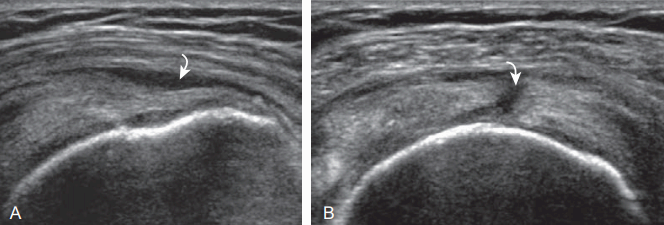

supraspinatus : partial -thickness tear ( A:long axis B: short axis) 윤활주머니 쪽 부분째짐의 초음파소견은 기본적으로 관절 쪽 부분 째짐과 같고, 다만 손상 부위가 윤활주머니 쪽이라는 것이다. 힘줄이 윤활주머니 쪽에서 찢어져서 큰 거친 면으로 확장된 경우라도 관절 쪽 힘줄 손상이 없다면 윤활주머니 쪽 부분 째짐이다. 이때, 정상 힘줄의 볼록한 모양이 없어지기도 하고, 찢어진 힘줄 부위에 세모근과 활액낭이 움푹 내려앉은(함몰된) 것처럼 보인다. 역시 큰 거친 면 뼈겉질이 불규칙하게 보이는 것이 보통이다. 활액낭염의 윤활염증 조직이 같은 에코의 힘줄 째진 곳에 놓여서 힘줄 째짐과 가늘어짐이 뚜렷하지 않을 수 있다.